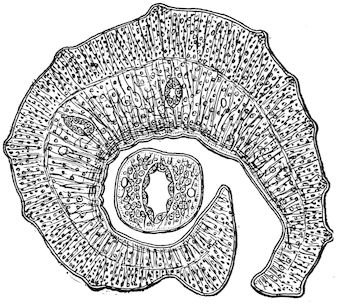

Fig. 8.—Transverse section through the middle region of the face in a pig suffering from osseous cachexia.

18In the final stages, the bones may be cut with a knife, and a time arrives when bony tissue seems completely to have disappeared; thus, as shown in Fig. 8 herewith, it was possible to cut the entire head of a pig into thin slices without the slightest difficulty. All parts of the head had been affected by the softening change.